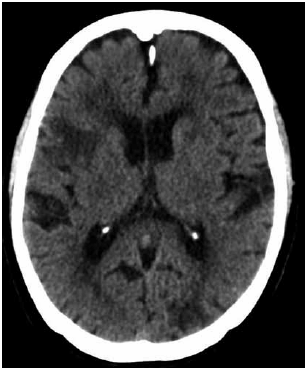

Paciente de 80 anos procura o consultório médico com queixa de esquecimentos e confusão mental há 3 anos. Seus déficits vinham piorando lenta e paulatinamente. Relata uma piora importante, de forma súbita, há cerca de 2 anos, quando apresentou um desvio de rima labial para direita e diminuição da força muscular do membro superior esquerdo. Concomitantemente, paciente deixou de cozinhar por deixar a comida queimar no fogo. Deixou de realizar compras na feira porque esquecia do que precisava comprar e se atrapalhava com os pagamentos. Tornou-se apática, desinteressada, triste e vem se isolando socialmente.

Paciente mantém-se independente para as atividades básicas, mas tem comprometimento para as atividades instrumentais.

Vem apresentando diminuição da velocidade de marcha, autorrelato de cansaço e força de preensão palmar de 12 Kgf.

Medicação de uso continuado: ácido acetilsalicílico 100 mg após o almoço, atorvastatina 40 mg uma vez ao dia, memantina 10 mg 1x/d, donepezila 10 mg 1x/d, losartana 50 mg 12/12h, atenolol 25 mg 12/12h, insulina NPH 6 unidades por via subcutânea pela manhã e à noite, metformina 850 mg 3x/d, gliclazida 60 mg 1x/d e evogliptina 5 mg pela manhã.

A paciente realizou uma tomografia computadorizada de crânio.

(Arquivo pessoal; imagem usada com autorização)